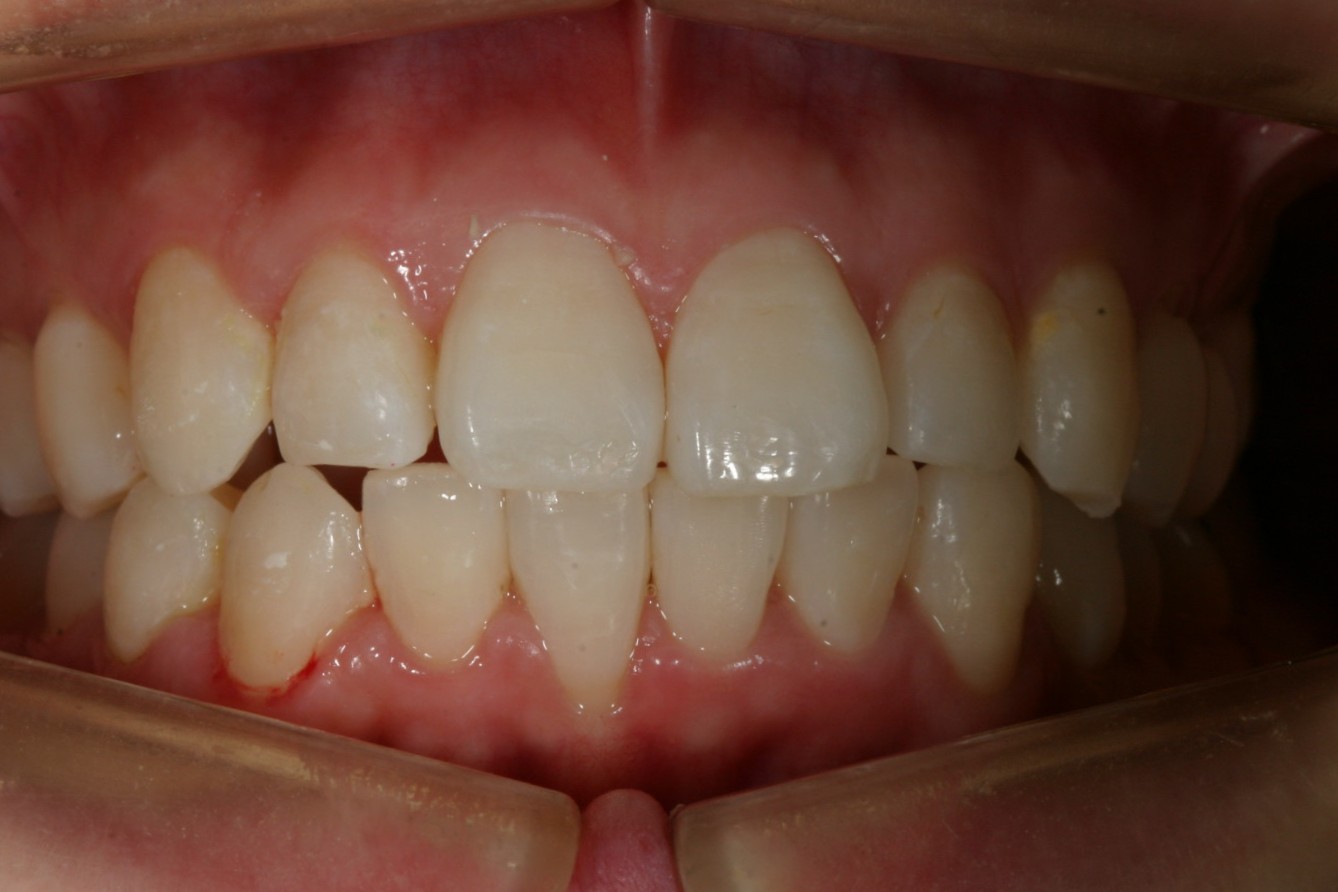

その後半年でここまで改善です。 前から見るとこんな感じです。 ここから再度インビザラインで最終調整です。

綺麗に改善しました。

下顎のガタガタも綺麗に改善しました。

オーバージェットも綺麗になっています。